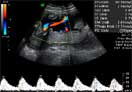

Ecografía Embarazo 2D y 3D